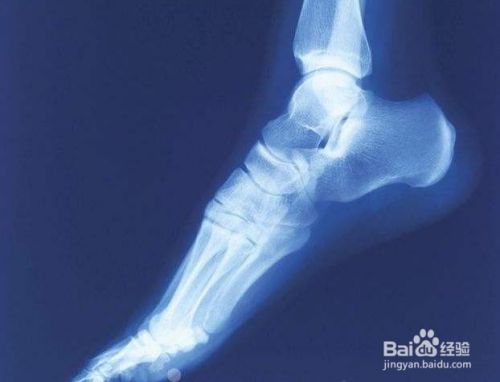

这个代夫家里的确没有门脸,就是在自己家里,有个黑黑的屋子里面还有陈旧的设备,用来拍片子的,要不是乡亲还真怕是上当受骗,简单了解了情况之后,又拍了个片子,他说你这骨伤只少得七八年以上了,怎么现在才来看,骨缝里都长上肉了,可不人家要给你开刀,骨头的端面都已经坏死了,长不到一起了,这个到你老了,弄好就残废了;